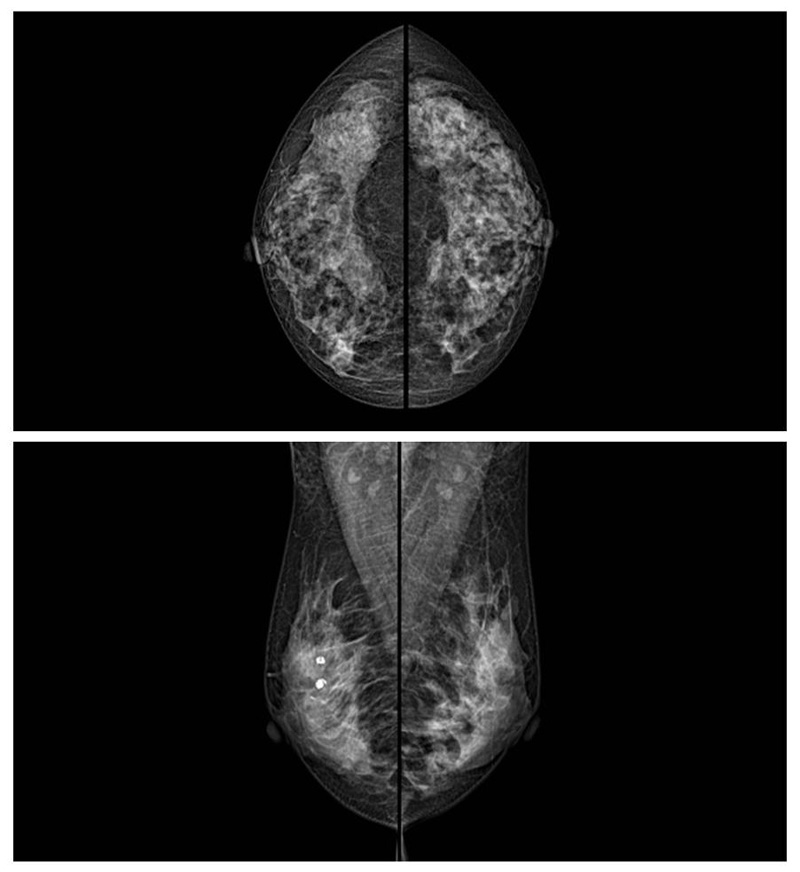

乳腺癌的發生率越來越高,已經是我們國家的癌癥之一已成為女性健康“頭號殺手”。乳腺DR可提高乳腺癌早期檢出率并精準定位。發現和診斷早期乳腺癌最有效的方法之一,明顯利大于弊女性都要重視乳腺的檢查。輻射很小最簡便、最可靠、無創性檢查手段,做一次乳腺DR的劑量相當于7周的正常生活。尤其是對于40歲以上的女性尤為重要,那么乳腺DR是怎么進行檢查的呢?我們來了解一下,為廣大朋友在檢查前有點心理準備。檢查時候是避開經期的前后,月經來后的7天左右比較合適。需要脫衣服檢查,根據拍片的擺位要求,有頭尾位置,內外斜位,還有側位。定點放大壓迫方法可以更細微清晰的檢查出病灶。